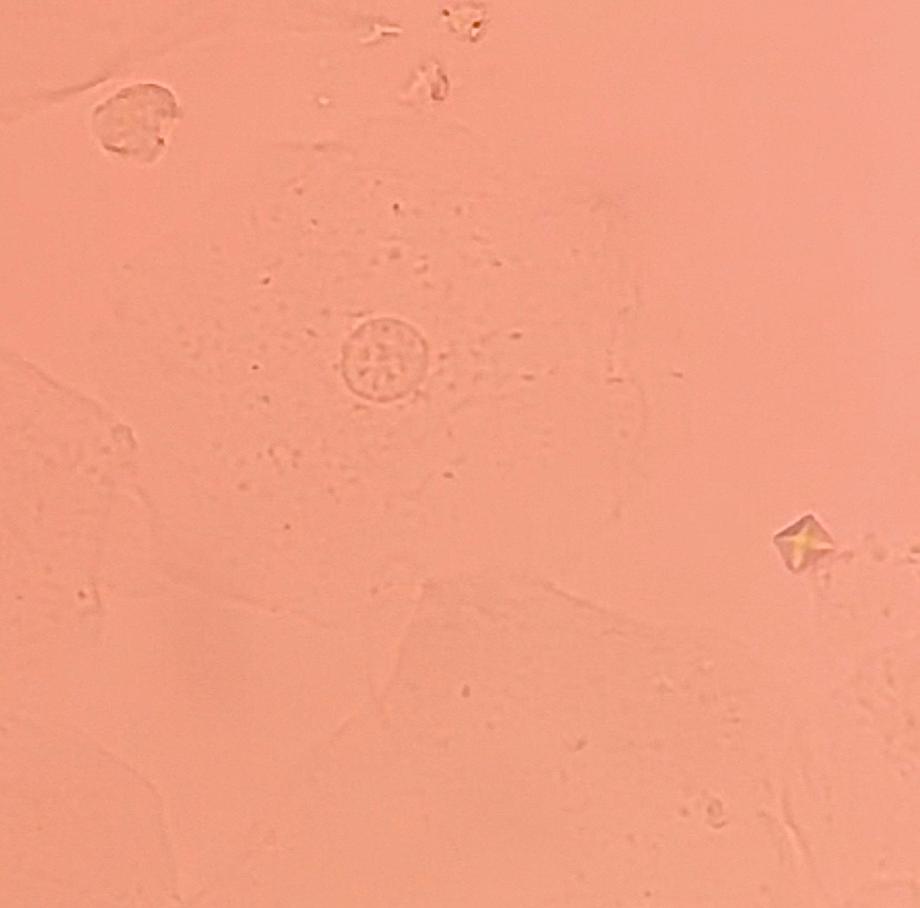

본문 시작 요 pH 측정 임상병리학과 394 2025-05-19 요 pH를 측정해본 후 산성뇨, 염기성뇨와 관련된 질병에 대해 알아보는 시간을 가졌습니다 목록 이전요시험지 테스트 다음 환자 검체를 이용한 요침사 검경 & 회식 만족도조사 만족도 조사 이 페이지에서 제공하는 정보에 대하여 만족하시나요? 매우만족 만족 보통 불만족 매우불만족